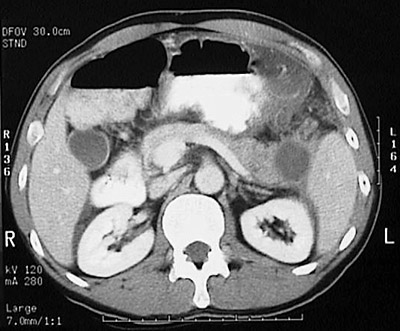

| This abdominal CT scan with contrast reveals a pancreatic pseudocyst, with a low attenuation liquefied center. This lesion is located in the tail of the pancreas next to the spleen. Inflammation with fluid collection extends to the adjacent omentum near the stomach. A pancreatic pseudocyst is a serious complication of pancreatitis. |